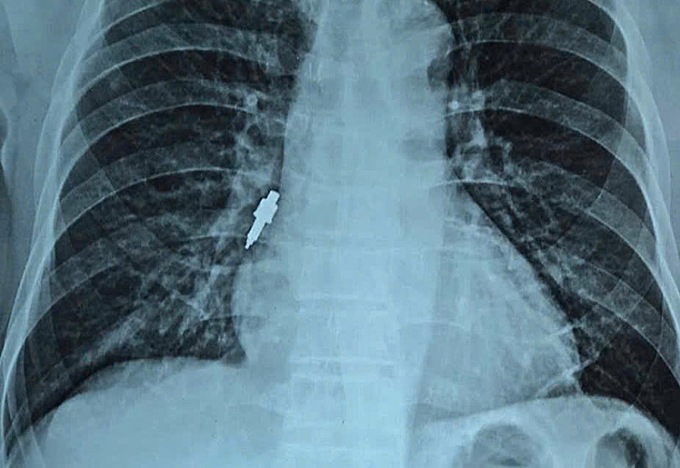

Dị vật kim loại nằm sâu trong đường thở. Ảnh: Bệnh viện cung cấp

Ngày 26/11, đại diện viện cho biết nội soi gắp thành công dị vật nằm sâu trong phế quản phải của bệnh nhân. Dị vật là một dụng cụ nha khoa bằng inox, trơn nhẵn, dài 2,5 cm và có đường kính lớn nhất lên tới 1 cm.